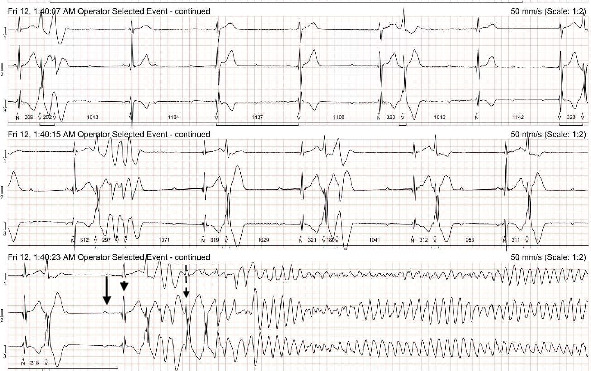

Objective: The objective of the study is to report a case of a dog that experienced sudden cardiac death due to ventricular fibrillation following a packed red cell transfusion. Case Summary: A 14-year-old, male castrated, American Staffordshire terrier dog was evaluated before a planned anesthetic event and was diagnosed with second-degree atrioventricular block. One week after the initial evaluation, the dog presented to an emergency facility for episodes of collapse and was diagnosed with hemoperitoneum secondary to splenic rupture. An emergency splenectomy was performed, but the dog developed regenerative anemia postsurgery and received a packed red blood cell transfusion. A Holter monitor was placed before the start of the transfusion due to concerns about previous rhythm abnormalities. Two hours after the blood transfusion, the dog experienced sudden cardiac arrest, and closed-chest cardiopulmonary resuscitation was unsuccessful. Analysis of the Holter recording revealed the onset of ventricular arrhythmias following transfusion that progressed to frequent polymorphic ventricular tachycardia and ventricular fibrillation. Additionally, QT interval prolongation was noted just before the onset of the ventricular arrhythmias on the Holter recording. New Information Provided: To the authors' knowledge, this is the first report of a dog that suffered sudden cardiac death after a blood transfusion and discusses possible causes of ventricular arrhythmias.